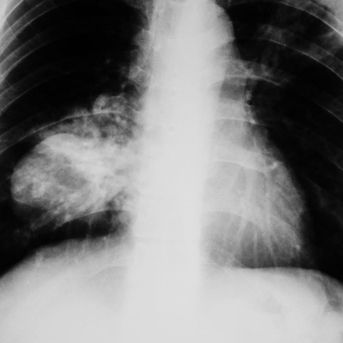

Linfocitos B más maduros mejoran la respuesta a la quimio-inmunoterapia en cáncer de pulmón

Un trabajo del Grupo Español de Cáncer de Pulmón (GECP) ha constatado que los pacientes con cáncer de pulmón que obtienen mejores resultados con la quimio-inmunoterapia administrada antes de la cirugía presentan linfocitos B más maduros y funcionales, responsables de la producción de anticuerpos.La investigación confirma que los linfocitos B,...`>